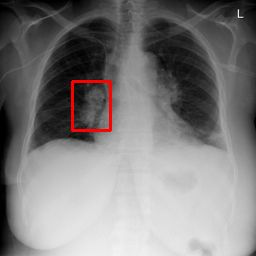

Deployments of artificial intelligence in medical diagnostics mandate not just accuracy and efficacy but also trust, emphasizing the need for explainability in machine decisions. The recent trend in automated medical image diagnostics leans towards the deployment of Transformer-based architectures, credited to their impressive capabilities. Since the self-attention feature of transformers contributes towards identifying crucial regions during the classification process, they enhance the trustability of the methods. However, the complex intricacies of these attention mechanisms may fall short of effectively pinpointing the regions of interest directly influencing AI decisions. Our research endeavors to innovate a unique attention block that underscores the correlation between 'regions' rather than 'pixels'. To address this challenge, we introduce an innovative system grounded in prototype learning, featuring an advanced self-attention mechanism that goes beyond conventional ad-hoc visual explanation techniques by offering comprehensible visual insights. A combined quantitative and qualitative methodological approach was used to demonstrate the effectiveness of the proposed method on the large-scale NIH chest X-ray dataset. Experimental results showed that our proposed method offers a promising direction for explainability, which can lead to the development of more trustable systems, which can facilitate easier and rapid adoption of such technology into routine clinics. The code is available at www.github.com/NUBagcilab/r2r_proto.